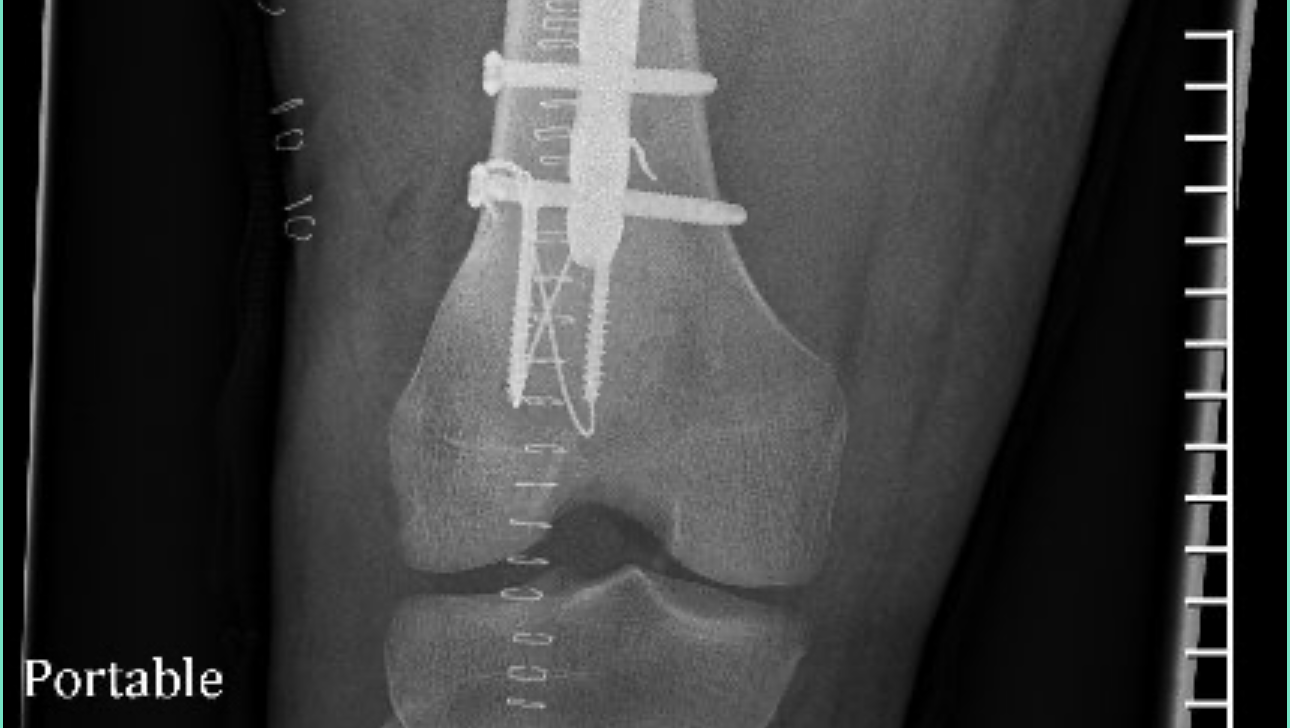

Once at the hospital, it was determined that he broke both of his arms and legs in multiple places, shattered his knee cap, broke his ribs, broke and dislocated his hip, and broke his femur. The only thing not broken is his spirit, pretty face, and desire to face this battle head on. Despite only being able to wiggle his fingers and toes, he still keeps us and the wonderful hospital staff laughing and is a true inspiration.

Brandon has been hospitalized since the accident and following multiple surgeries and some gnarly titanium all throughout his body, he is preparing to go to a rehabilitation center/nursing home to continue healing with months of physical therapy as he is not anywhere near being self-sufficient.